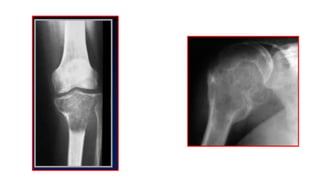

Extensa lesión osteolíticaubicada en tibia proximal con discretas

trabeculaciones en su interior, que adelgaza la cortical en la región

medial/condilo medial de la tibia proximal.

TC recon axial ventana ósea: en la imagen de tc se comprueba que el tumor

invade y destruye la cortical de la porción medial de tibia proximal/ RM

sagital lesión lítica isointensa con destrucción de la cortical